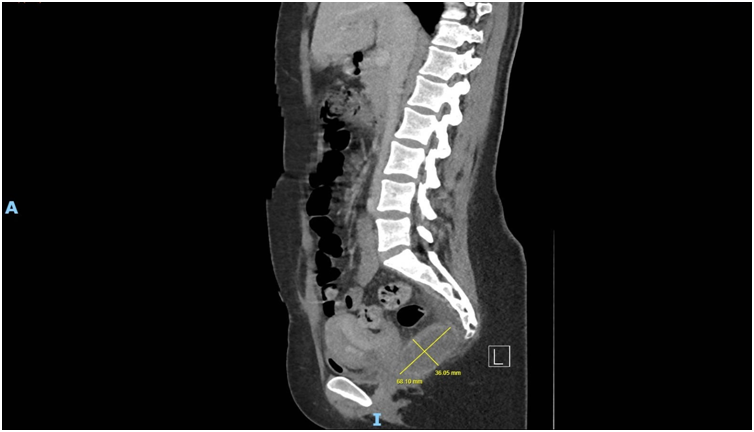

Imaging via MRI and CT demonstrated a complex, encapsulated lesion with peripheral enhancement and restricted diffusion. Multidisciplinary evaluation suggested a congenital epidermoid or duplication cyst. Given the absence of malignancy and surgical complexity, a conservative management strategy was adopted.

Figure 6: Figure 6 Duplication cyst 2025 sagittal plane

Figure 8: Figure 8 Duplication cyst 2020 axial plane